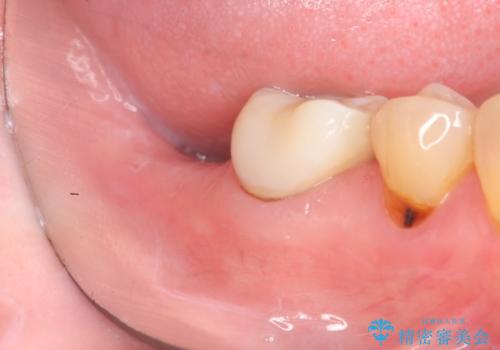

奥歯 インプラントによる機能回復

- 歯を欠損し、噛めないことの治療を希望され来院されました。

インプラントを用いて、しっかりとかめるような治療を計画します。

最後方臼歯はインプラントを用いることでしっかりと咬合機能を回復することができます。